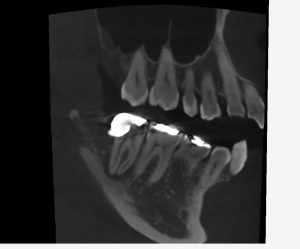

レントゲンを見てみよう。

(術前のレントゲン、CT)

半埋伏智歯(半分歯茎の中に埋まっている親知らず)の影響で、右下7番の遠心にう蝕があったであろうことが分かる。

この場所は、親知らずが無ければ、本来虫歯ができるはずがない場所だ。

このようなことがあるので、半埋伏智歯は早めに抜いておいた方が良いのかもしれない。

一つ言えることは、この場所に虫歯ができると「治療が非常に難しくなる」ということである。

理由は簡単、見えにくいからだ。

現に過去の虫歯治療の状態は、問題だらけだ。

・虫歯も取りきれていない

・裏層したセメントは大きくはみ出している

・修復物の適合も全くあっていない

見えない場所を、盲目的に、感覚頼りに治療したのだろう。

そして、結果的に神経が死んでしまい、かなり広範囲に骨が溶けてしまっている。